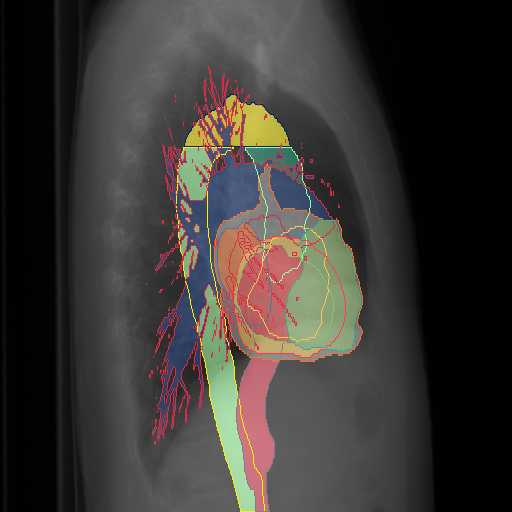

We display qualitative results in Fig. 3. The annotators tend to be content with most annotations. There are edits at the extensions of the esophagus, trachea, and aorta and corrections of the lower ribs. There is little consensus for classes in the abdominal area, such as the stomach, as seen on the right of Fig. 3 . In contrast, the annotators often align for bone classes.

We show the quantitative segmentation performance against medical expert annotations for all classes in Fig. 3 . The dashed lines represent the IAA, whereas the dotted line displays the average MAA. As the task for the human annotators was not to annotate from scratch but to correct wrong pixel-wise predictions, we can see a high MAA for most classes. In the frontal view, the most significant disagreements exist for rare bone structures such as L3 and C4, lower ribs, the mediastinal distribution, or the breast tissue. The IAA and MAA are highly similar with mIoU of respective 95% and 94%. The Hausdorff distance for MAA is slightly lower than the IAA, indicating slight differences in boundary annotations while maintaining a considerable overlap with the other annotator. In the lateral view, the concrete delineation of rib structures appears ambiguous, leading to lower MAA and IAA with a greater IAA than MAA for all metrics in this supercategory. Overall there is less agreement between the medical experts in the lateral view, leading to a better average MAA than IAA across all metrics (i.e. 85% vs 83% mIoU). While the experts propose changes to the original predictions, they are often not overlapping. In the lateral view, rib segmentations can become quite hard to interpret. While both annotators disagree with the rib segmentations, they do not always agree on how they should look. Similarly to the frontal view, tube-like structures like the esophagus are extended as they can appear fractured at times.